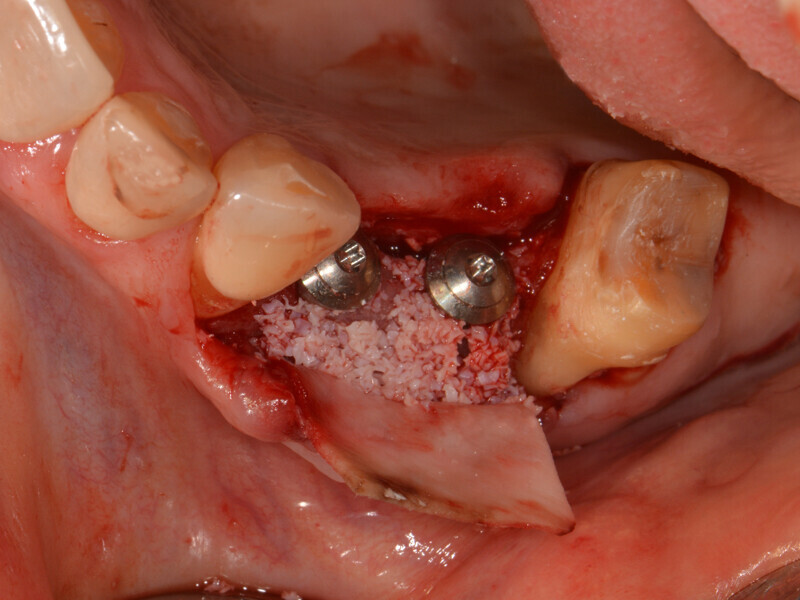

After local anaesthesia, a mid-crestal incision was performed and a mucoperiosteal flap was raised (Fig. 8). The flap design should be chosen such that the flap will not affect the positioning of the surgical guide. The osseous situation corresponded to the CBCT findings of a buccally atrophied alveolar ridge. After pilot drilling, the fully guided preparation was performed in accordance with the drilling protocol (Fig. 9). The vertical drilling up to just before the maxillary sinus was controlled by the surgical guide. The cortical bone of the sinus floor could then be selectively fractured using osteotomes and the Schneiderian membrane lifted to 11 mm, and subsequently bone substitute material was inserted (Bio-Oss, Geistlich; Fig. 10). After placement of the implants (Figs. 11 & 12), the buccal atrophy in regions #14 and 15 was reconstructed with bone substitute material and covered with a resorbable membrane (Bio-Gide, Geistlich; Fig. 13). Saliva-proof wound closure was performed using e-PTFE suture material.

Fig. 10: Insertion of bone substitute material.

Fig. 11: Placement of the implants in regions #14 and 15.